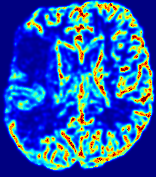

LesionRefer to captionRefer to captionRefer to captionRefer to captionRefer to captionRefer to caption𝐕rgbsubscript𝐕𝑟𝑔𝑏{\bf{V}}_{rgb}Refer to captionRefer to captionRefer to captionRefer to captionRefer to captionRefer to caption𝐕2subscriptnorm𝐕2{\|\bf{V}}\|_{2}Refer to captionRefer to captionRefer to captionRefer to captionRefer to captionRefer to captionRefer to caption3.53.53.52.82.82.82.12.12.11.41.41.40.70.70.70.00.00.0(mm/s)𝑚𝑚𝑠(mm/s)D𝐷DRefer to captionRefer to captionRefer to captionRefer to captionRefer to captionRefer to captionRefer to caption0.0200.0200.0200.0160.0160.0160.0120.0120.0120.0080.0080.0080.0040.0040.0040.0000.0000.000(mm2/s)𝑚superscript𝑚2𝑠(mm^{2}/s)Slice #1Slice #2Slice #3Slice #4Slice #5Slice #6

Figure 3: PIANO feature maps for one stroke patient, where the lesion is located in the left hemisphere. Top row: segmented stroke lesion region (white) on different slices, obtained from ISLES 2017. The corresponding slices for the PIANO feature maps are shown in the following rows.

For a better insight into an estimated velocity field 𝐕𝐕{\bf{V}} and diffusion field 𝐃𝐃{\bf{D}}, we compute the following maps: (1) 𝐕rgbsubscript𝐕𝑟𝑔𝑏{\bf{V}}_{rgb}: Color-coded orientation map of 𝐕=(Vx,Vy,Vz)T𝐕superscriptsuperscript𝑉𝑥superscript𝑉𝑦superscript𝑉𝑧𝑇{\bf{V}}=(V^{x},V^{y},V^{z})^{T}, obtained by normalizing 𝐕𝐕{\bf{V}} to unit length and mapping its 3 components to red, green, blue respectively; (2) 𝐕2subscriptnorm𝐕2\|{\bf{V}}\|_{2}: 222 norm of 𝐕𝐕{\bf{V}}; (3) D𝐷D: scalar field in Eq. 5.

Fig. 3 and Fig. 4 show the PIANO feature maps estimated from two ISLES 2017 patients: all are highly consistent with the lesion in both cases. Details of the blood flow trajectories are revealed in 𝐕rgbsubscript𝐕𝑟𝑔𝑏{\bf{V}}_{rgb} by the ridged patterns and the sharp changes of colors in the unaffected (right) hemisphere, while the flat patterns appearing within the lesion provide little directional information about the velocity and indicate low velocity magnitudes. Velocity magnitudes are more directly visualized via 𝐕2subscriptnorm𝐕2\|{\bf{V}}\|_{2}, from which one can easily locate the lesion where 𝐕2subscriptnorm𝐕2\|{\bf{V}}\|_{2} is low. D𝐷D also indicates lower diffusion values in the lesion, though with less contrast potentially due to the fact that it captures the accumulated effect of CA diffusion at the voxel-level.